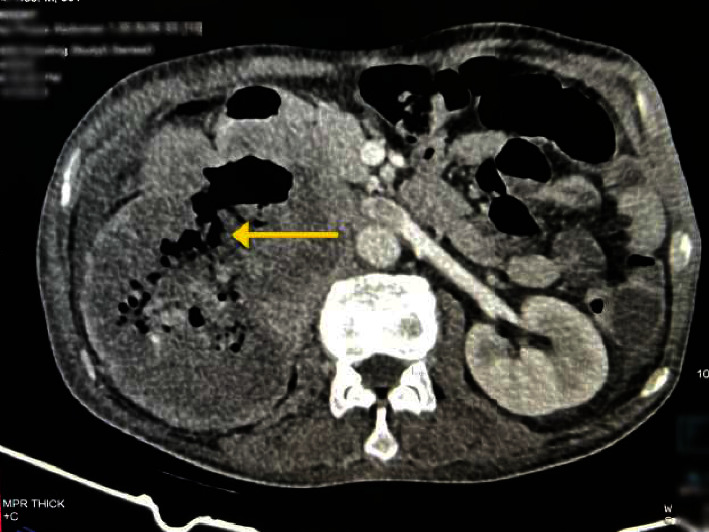

急性上消化道出血(UGIB)是一种医疗急症,最常见的病因是消化性溃疡病(PUD)或静脉曲张出血。然而,通过侵犯小肠引起 UGIB 的癌症并不常见,而肾细胞癌(RCC)侵犯十二指肠的情况更是罕见。一名 55 岁的男性患者出现血便和右侧腹痛。食管胃十二指肠镜检查(EGD)发现十二指肠内有活动性出血源,后经造影剂增强计算机断层扫描(CECT)确定为 RCC 直接延伸引起的十二指肠瘘(DRF)。影像学检查证实存在浸润邻近器官的恶性肾肿块。这种RCC伴有DRF并表现为UGIB的非典型表现强调了对消化道出血病例进行全面评估以确定罕见潜在病因的重要性。

Acute upper gastrointestinal bleeding (UGIB) is a medical emergency with most common cause being peptic ulcer disease (PUD) or variceal bleeding. However, cancers that cause UGIB by invading the small intestine are uncommon, and the invasion of renal cell carcinoma (RCC) into the duodenum is an even rarer occurrence. A 55-year-old male presented with melena and right flank pain. Esophagogastroduodenoscopy (EGD) revealed an active bleeding source in the duodenum, later identified on contrast-enhanced computed tomography (CECT) as a duodenorenal fistula (DRF) caused by direct extension of the RCC. The imaging confirmed the presence of a malignant renal mass infiltrating adjacent organs. This atypical presentation of RCC with DRF manifesting as UGIB underscores the importance of comprehensive evaluations in cases of gastrointestinal bleeding to identify rare underlying causes.